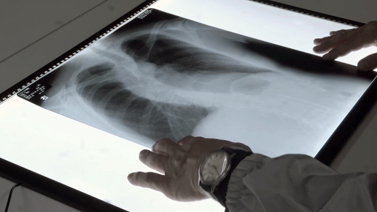

保管義務のある重要書類、大判のA0サイズ図面、医療関連書類など、各種規制やガイドラインに準拠した最適なソリューションをご提案。

2.電子化作業 スキャン内容に応じてADF(自動送スキャン)やフラットベッドなど最適な機種を選定し、電子化を行います。